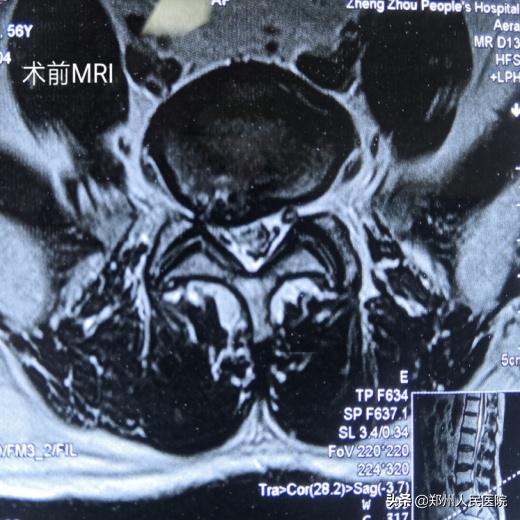

56岁的刘叔有着和小葛一样的困扰,而且他的症状更严重,病程时间更长。腰部疼痛伴右下肢放射痛麻木8年,加重伴间歇性跛行1个月,右足跟、足底及足外侧的皮肤痛触觉减退,右足的跖屈及右足趾背伸肌力也明显下降,平日里连日常遛弯走上几百米都成了奢望。

为刘叔进行的“单侧双通道UBE脊柱内镜术”在不足两个小时后顺利结束,术中麻醉效果极佳,出血量只有数十毫升,清晰放大的视野下,突出的髓核及增厚的黄韧带完全摘除,骨性狭窄磨钻安全扩大减压,偶尔出现的小出血点也在射频刀头的控制下立即止血,轻松漂浮的神经根又重新出现了。